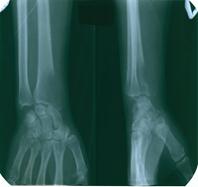

![]() | |||

Рис.6. Эндопротез дистальной части лучевой кости.

Рис.5 Эндопротез локтевого сустава